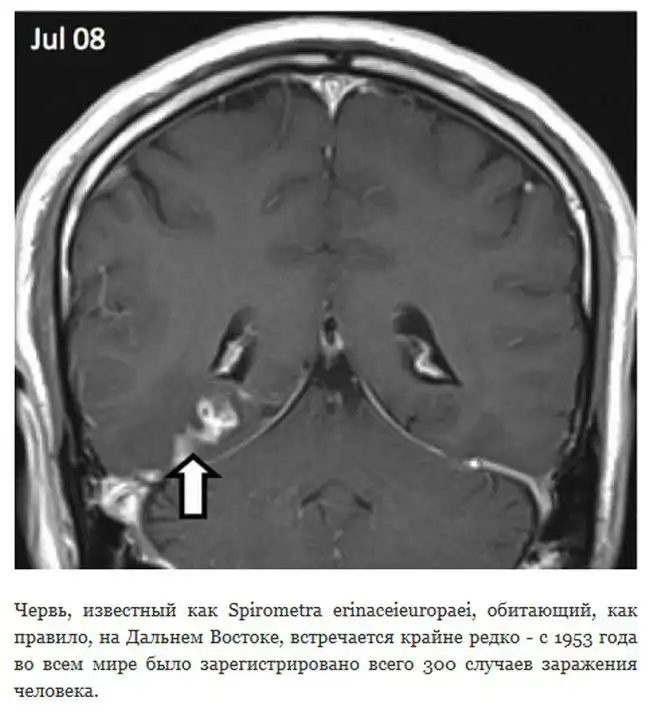

В Великобритании исследования одного пациента показали, что живущий в его мозге червь смог преодолеть расстояние в 5 сантиметров, от правого края до центра. Для того, чтобы продвинуться на такое расстояние, сантиметровому цепню понадобилось целых четыре года.